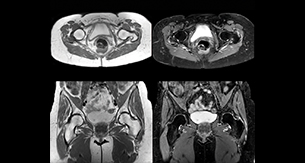

“In peripheral joints, mDIXON TSE imaging aids in diagnosing injuries in ligaments or tendons, for imaging degenerative and inflammatory pathologies such as osteoarthritis and rheumatologic disorders and for oncological exploration.” “For tendon and ligament assessment around knee, ankle, hip and elbow, mDIXON TSE contributes to diagnostic confidence thanks to having images both with and without fat suppression – and without time penalty. This is possible because 2-point mDIXON is faster than the common 3-point Dixon method. It can also increase efficiency as it helps avoid having to add scans during the exam.”

“In peripheral joints, we get good image quality in difficult areas with mDIXON TSE.

Fat suppressed images appear homogeneous over the entire image, even with large coverage at 3.0T – for instance in scapular or hip girdles – or in the bearing areas or around metal prostheses, where fat suppression is often deficient with STIR or spectral fat suppression, causing diagnostic difficulties. If a diagnostic image is right the first time, we don’t need to repeat or add a sequence.” “mDIXON TSE sequences allow simultaneous characterization of morphological changes from the in-phase T2-weighted images and visualization of edematous changes, thanks to the water T2-weighted images from the same acquisition. Anatomical and morphological considerations could be a partial or complete ligament tear, a bony avulsion or hematoma.” “For soft tissue assessment mDIXON brings similar benefits. For example in one T2-weighted mDIXON TSE acquisition, having the multiple contrasts helps us assess abnormalities in peripheral nerves fascicles, which may be due to anatomical or inflammatory changes..”